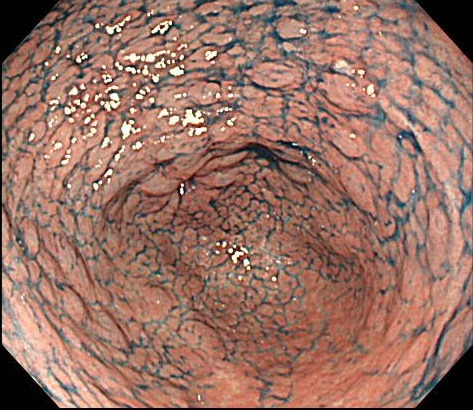

위내시경 조직검사는 단순히 암을 확인하는 절차가 아니라, 위 점막의 상태를 세포 수준에서 분석하여 정확한 진단과 치료 계획을 세우기 위한 핵심 과정입니다. 위 점막 변화는 언뜻 보기에는 정상처럼 보이지만, 만성염증의 단계, 세포 변형 정도, 미세한 종양성 변화 등이 포함되어 있을 수 있기 때문에 조직학적 확인이 반드시 필요합니다.

- 표면이 거칠거나 미세한 융기, 함몰이 발견되는 경우

- 장상피화생이 의심되는 구조 변화가 있는 경우

위내시경에서 보이는 병변은 일반적으로 ‘정상’, ‘염증’, ‘선종’, ‘암’으로 구분되지만, 실제 점막 내부의 세포 변화는 훨씬 다양하고 복잡합니다. 육안 관찰만으로 선종인지 단순 염증인지, 조기 위암인지 구분이 어려운 경우가 많기 때문에 조직검사가 정확한 확진을 내리게 됩니다.